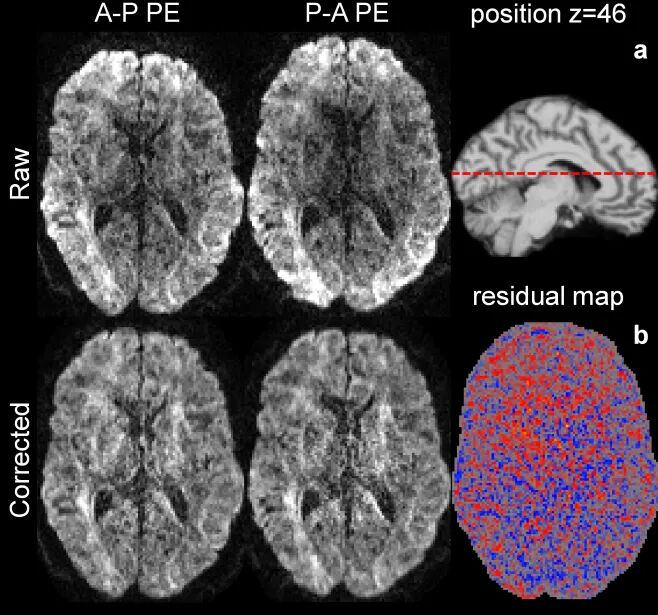

值得注意的是,Noise2Average 框架实现了与常规扫描流程的无缝兼容。它无需额外的采集步骤,而是巧妙挖掘了成像数据的内在冗余——利用多回波成像中的不同回波的图像、平面回波成像中的相反相位编码数据,以及基于物理模型合成的配对图像,构建了高效的训练数据对。

相反相位编码图像作为网络训练输入